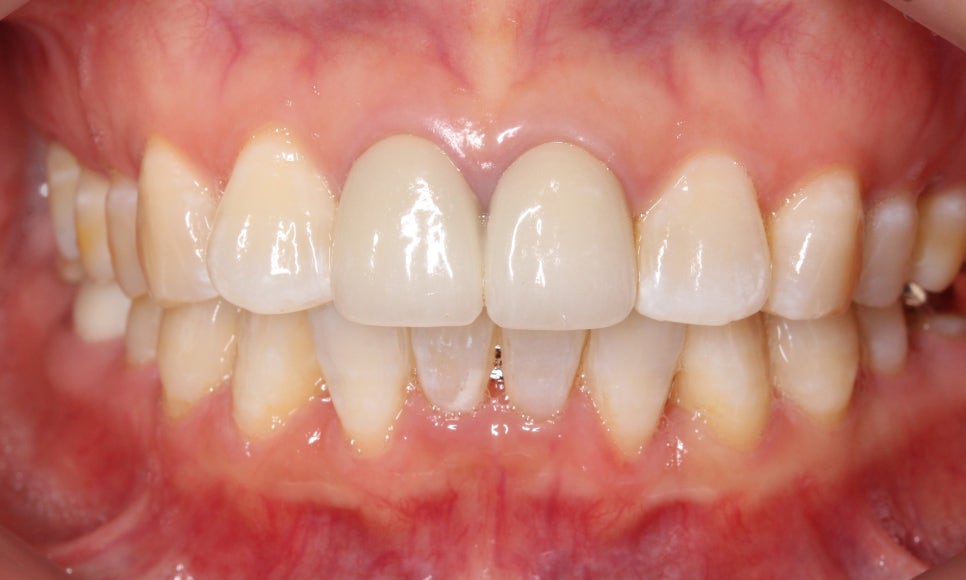

약 9개월의 아랫니 부분교정이 끝난 뒤

치아의 모습입니다~

삐뚤거리던 아랫니가 많이 정리된 모습이죠?

들쭉날쭉하던 아랫니의 전치부도

아랫니 부분교정(2D교정)으로

고르게 맞춰진 모습입니다!